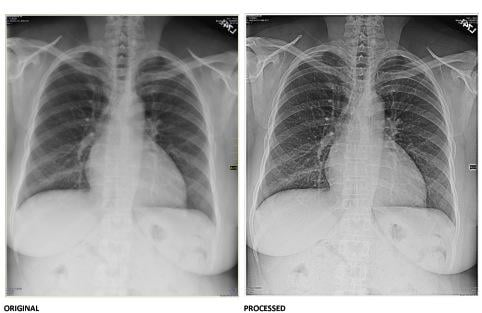

Standard x-ray image before (left) and after (right) Digital Harmonic's technology is applied. Image courtesy of Business Wire.

The new company, Digital Harmonic LLC, has developed a proprietary and patented image and waveform technology that aims to revolutionize how the medical community implements X-rays. The company has already raised $5 million and is seeking to raise another $5 million to fund its growth.

“We figured out how to extract previously undetected data out of complex sound waveforms and then applied that new theory to create remarkably detailed images,” said Smith. “The potential for the medical community to be able to get much more precise images is exciting.”